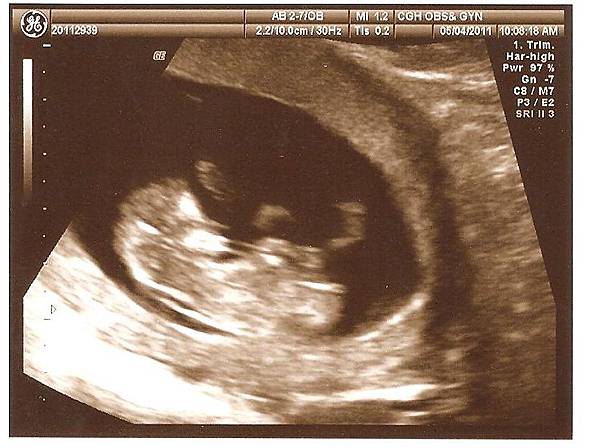

上周產檢時照超音波,看到小兔可愛的樣子囉

小手小腳不停揮舞,感覺也是個活潑的寶寶

不過比起貝貝才12W產檢時,就不停整個人在羊水裡開心的上下跳動,醫生還要等他不那麼high時才照的到超音波,小兔算是比較文靜的了